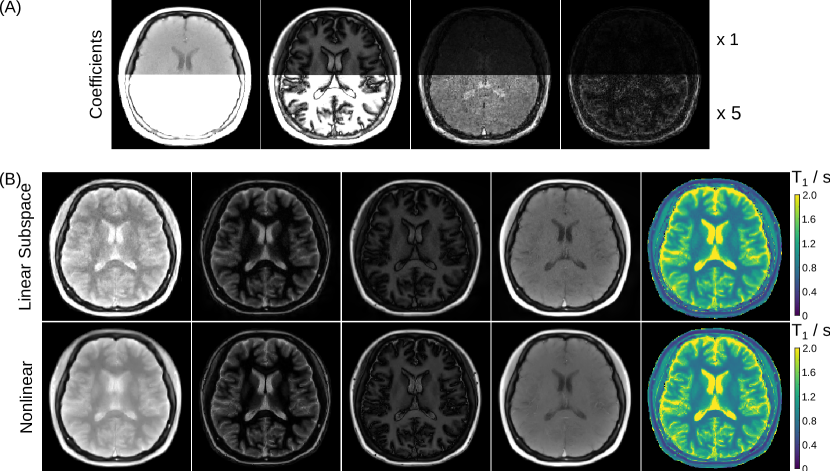

Refer to caption

Figure 2: (A). (Leftmost) Model-based reconstructed T1 map and (left middle) the ROI-analysed quantitative T1 values for the numerical phantom using the single-shot IR radial FLASH sequence. (Right middle and rightmost) Similar results for T2 mapping using the multi-echo spin-echo sequence. (B). (Top) The reconstructed parameter maps (Mss,M0,R1)Tsuperscriptsubscript𝑀𝑠𝑠subscript𝑀0superscriptsubscript𝑅1𝑇(M_{ss},M_{0},R_{1}^{*})^{T} for the T1 model and (bottom) (M0,R2)Tsuperscriptsubscript𝑀0subscript𝑅2𝑇(M_{0},R_{2})^{T} for the T2 model with the corresponding T1 / T2 maps in the rightmost column.

Quantitative parameter maps for both acquisitions are estimated using the nonlinear model-based reconstruction. In other words, the estimation of parameter maps (Mss,M0,R1)Tsuperscriptsubscript𝑀𝑠𝑠subscript𝑀0superscriptsubscript𝑅1𝑇(M_{ss},M_{0},R_{1}^{*})^{T} or parameter maps (M0,R2)Tsuperscriptsubscriptsuperscript𝑀0subscript𝑅2𝑇(M^{\prime}_{0},R_{2})^{T}, respectively, and coil sensitivity maps (c1,,cN)Tsuperscriptsubscript𝑐1subscript𝑐𝑁𝑇(c_{1},\ldots,c_{N})^{T} is formulated as a nonlinear inverse problem with a joint 1subscript1\ell_{1}-Wavelet regularization applied to the parameter maps and the Sobolev norm [41] to the coil sensitivity maps. This nonlinear inverse problem is then solved by the IRGNM-FISTA algorithm [13]. After estimation of the parameters T1subscript𝑇1T_{1} and T2subscript𝑇2T_{2} maps can be calculated. Note that the M0subscript𝑀0M_{0} and M0subscriptsuperscript𝑀0M^{\prime}_{0} absorb physical effects which are not explicitely modelled and identical over all inversion or echo times.

To evaluate the quantitative accuracy of the model-based methods, numerical phantoms with different T1 relaxation times (ranging from 200 ms to 2000 ms with a step size of 200 ms for each tube, and 3000 ms for the background), T2 relaxation times (ranging from 20 ms to 200 ms with a step size of 20 ms for each tube, and 1000 ms for the background) were simulated, respectively. To avoid an inverse crime [42], the k𝑘k-space data was derived from the analytical Fourier representation of an ellipse assuming an array of eight circular receiver coils surrounding the phantom without overlap. Complex white Gaussian noise with a moderate standard deviation was added to the simulated k𝑘k-space data.

Fig. 2 (A) presents the estimated T1, T2 maps and the corresponding ROI-analyzed quantitative values for the numerical phantom using model-based reconstructions. Good quantitative accuracy is confirmed for both model-based T1 and T2 mapping methods. Fig. 2 (B) demonstrates model-based reconstructed three and two physical parameter maps, the corresponding T1 and T2 maps for the retrospective T1 and T2 models on human brain studies. Further, synthetic images were computed for all inversion/echo times and the image series was then converted into movies showing the contrast changes in Supplementary Videos 1 and 2. For the data presented here, model-based T1 and T2 reconstruction took around 6 and 3 minutes on a GPU (Tesla V100 SXM2, NVIDIA, Santa Clara, CA), respectively.